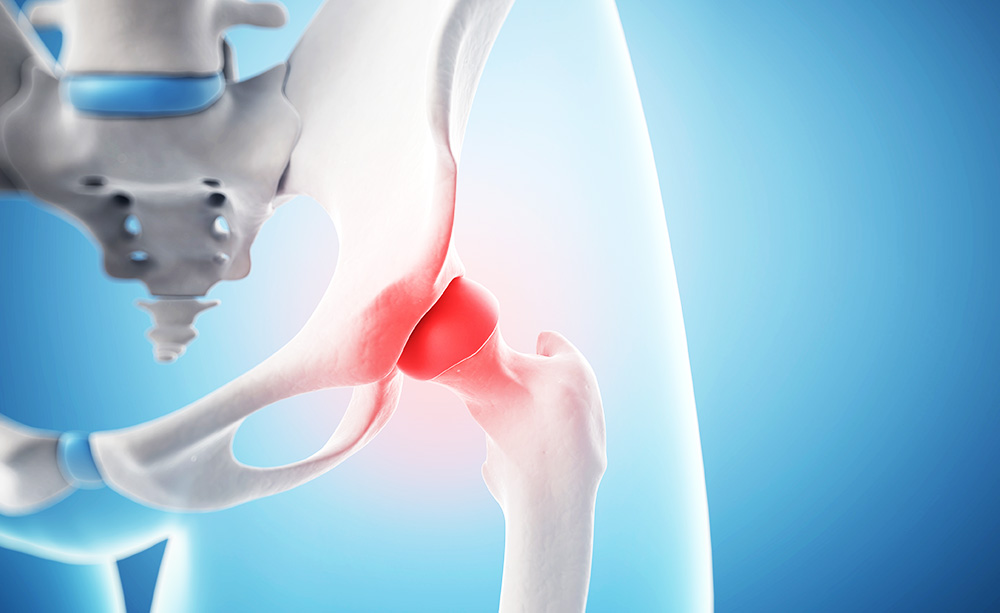

고관절은 엉덩이관절이라고도 불리우며, 보통 알고있는 골반위치에 있고, 공처럼 둥글게 생긴 대퇴골두가 글러브가 감싼듯한 모양으로 비구에 맞물려 있어요.

이렇듯 고관절은 오목하게 들어간 비구와 둥근 공모양의 대퇴골두로 이루어져 있으며 골반과 다리를 이어주는 우리 몸의 핵심 관절인데요. 그리고 고관절은 골반을 통해 전달되는 체중을 지탱해주고 걷기와 달리기같은 다리 운동들을 가능하게 해주는 관절이기도 해요.